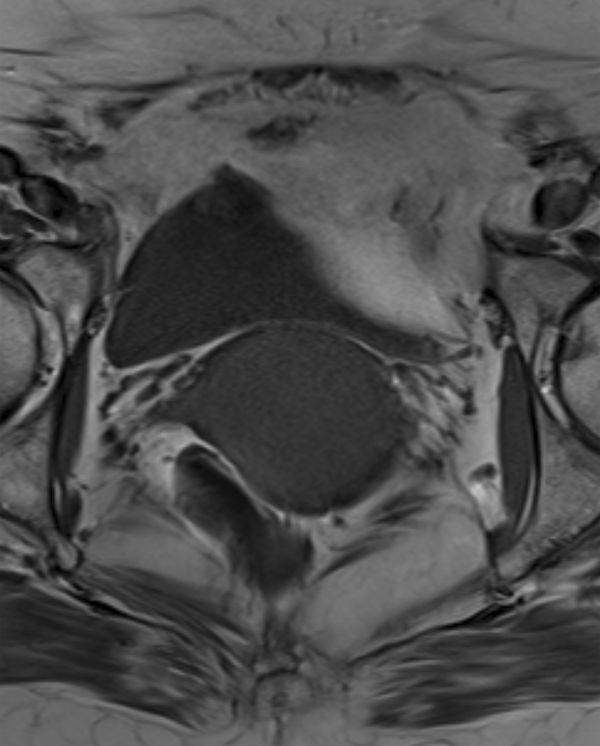

Superficial myofibroblastomas of the lower female genital tract are an unusual type of benign mesenchymal tumour. To the authors' knowledge, there has been no previous imaging description of a superficial myofibroblastoma in the literature. Here, we describe a case that presented with symptoms consistent with vaginal prolapse. However, a mass was palpable on clinical examination with unusual features on MRI. Following surgery, the histopathological features were considered consistent with superficial myofibroblastoma. By presenting the MRI and histological findings, we aim to raise awareness about this lesion so that it may be considered in the differential diagnosis of a vaginal mass.

女性下生殖道浅表肌成纤维细胞瘤是一种罕见的良性间叶性肿瘤。据作者所知,此前文献中尚无关于浅表肌成纤维细胞瘤的影像学描述。在此,我们描述一例表现出与阴道脱垂相符症状的病例。然而,临床检查可触及肿物,MRI表现具有异常特征。手术后,组织病理学特征被认为符合浅表肌成纤维细胞瘤。通过展示MRI和组织学检查结果,我们旨在提高对该病变的认识,以便在阴道肿物的鉴别诊断中考虑到它。